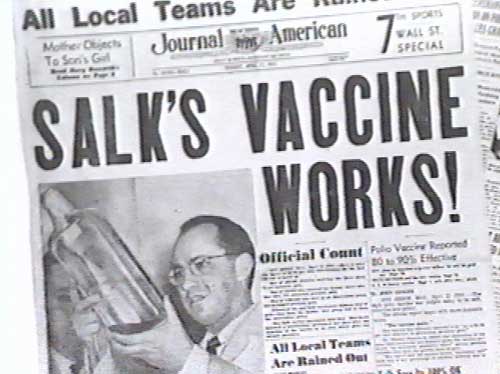

My Irish grandmother from Staten Island, NY told me three stories in my childhood that influence my practice of pediatrics and position on vaccines. The first story was how her only brother died at 4 years of age from an ear infection (perhaps pneumococcus bacteria). The second story involved a boy down the street from her, in 1953?, who was healthy on a Tuesday and in an iron lung machine on a Thursday, eventually dying from paralysis due to polio. The last story was the day her mother gathered her 4 daughters around her to tell them the news of the Salk vaccine breakthrough, and they danced and cried tears of joy.

My Irish grandmother from Staten Island, NY told me three stories in my childhood that influence my practice of pediatrics and position on vaccines. The first story was how her only brother died at 4 years of age from an ear infection (perhaps pneumococcus bacteria). The second story involved a boy down the street from her, in 1953?, who was healthy on a Tuesday and in an iron lung machine on a Thursday, eventually dying from paralysis due to polio. The last story was the day her mother gathered her 4 daughters around her to tell them the news of the Salk vaccine breakthrough, and they danced and cried tears of joy.

2. Vaccines for serious diseases have been developed over the decades to prevent children from ever contracting these serious diseases. The Salk polio vaccine developed in 1952, when there were 58,000 cases that year. The measles vaccine was licensed in US in 1964, yet world wide caused 630,000 deaths in 1990.